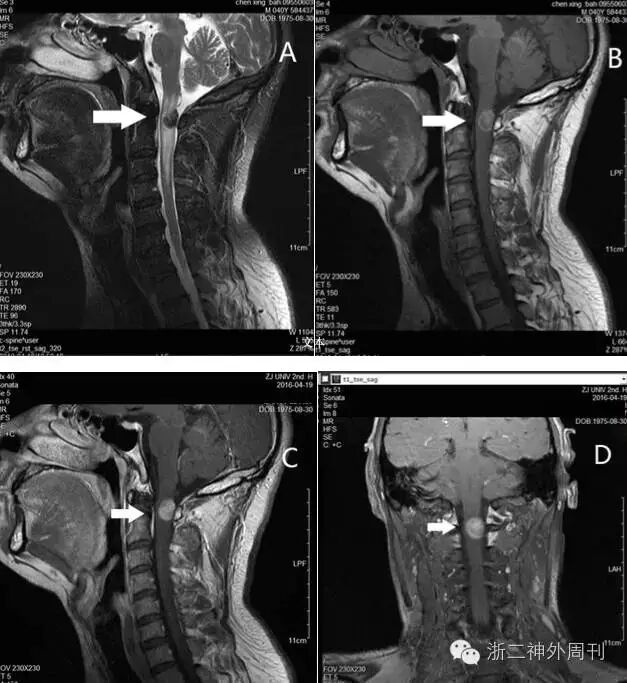

完善术前检查后,全麻下行椎管内病损切除术。术中神经电生理监测下,全椎板切开入路,剪开硬膜,即见黑色肿瘤匍匐于脊髓表面,向内嵌入脊髓深部,呈浸润性生长,与正常脊髓组织边界欠清。脊髓发出神经根处亦被肿瘤浸润包绕。肿瘤质地似橡胶样,切除困难,CUSA效果也不理想,最后使用刀片剜除中心部分肿瘤。术中冰冻提示黑色素性肿瘤,倾向转移性恶性黑色素瘤可能。此外,电生理监测提示肿瘤中心部分切除后电生理阈值略有下降,故仅做部分切除(图2)。术后标本送常规病理检查。

图2. 术中所见:A. 髓内肿瘤匍匐生长于脊髓背侧硬膜,大片黑色素沉积;B. 肿瘤质地极韧,似橡胶样,仅能用刀片剜除;C. 神经根受侵犯(箭头);D. 肿瘤浸润性生长,与正常脊髓边界不清(箭头),仅部分切除。